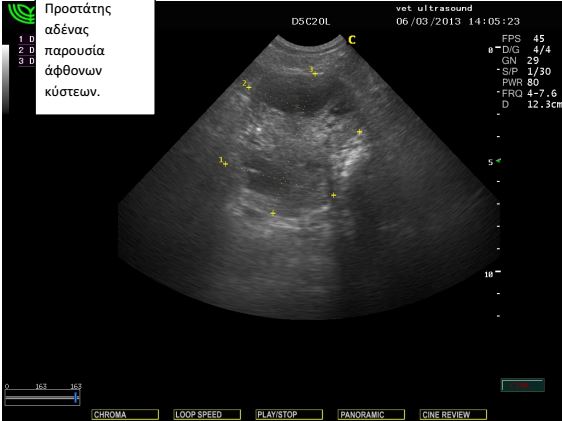

ραχιαία. Ο προστάτης ήταν διογκωμένος με παρουσία μεγάλων

κύστεων στο παρέγχυμά του. Τα υποσφυικά λεμφογάγγλια ήταν